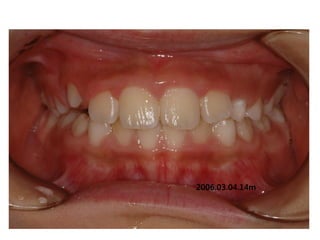

2006.03.04.14m

C.C

• Lower ant. crowding

Dx

• Deepbite, rhinitis, mentalis action

Goal

• Establish nose breathing and normal swallowing

pattern with T4K